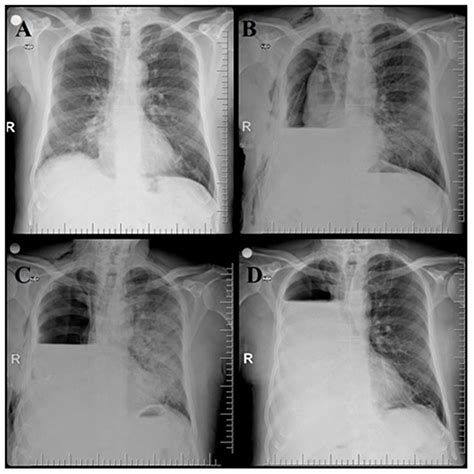

• Monitoring Progress: Doctors may order follow-up X-rays to ensure that the medication is working and that the inflammation is clearing up.

• Detecting Complications: It helps identify potential issues such as pleural effusion (fluid buildup around the lungs) or abscesses that may require different treatment approaches.

While a Pneumonia X-ray is the "gold standard" for initial diagnosis, it is not infallible. In some early stages of the disease, the X-ray might appear normal even if the patient is symptomatic. This is common in cases of "walking pneumonia" or very mild infections. If your clinical symptoms are severe but your X-ray is clear, your doctor may suggest further tests, such as a CT scan, blood work, or a pulse oximetry test to measure oxygen levels.

Furthermore, an X-ray can confirm the presence of pneumonia but does not always tell the doctor the specific cause—whether it is viral, bacterial, or fungal. This is why physicians often combine imaging results with physical examinations, listen to your lungs with a stethoscope, and consider your medical history before prescribing antibiotics or other treatments.